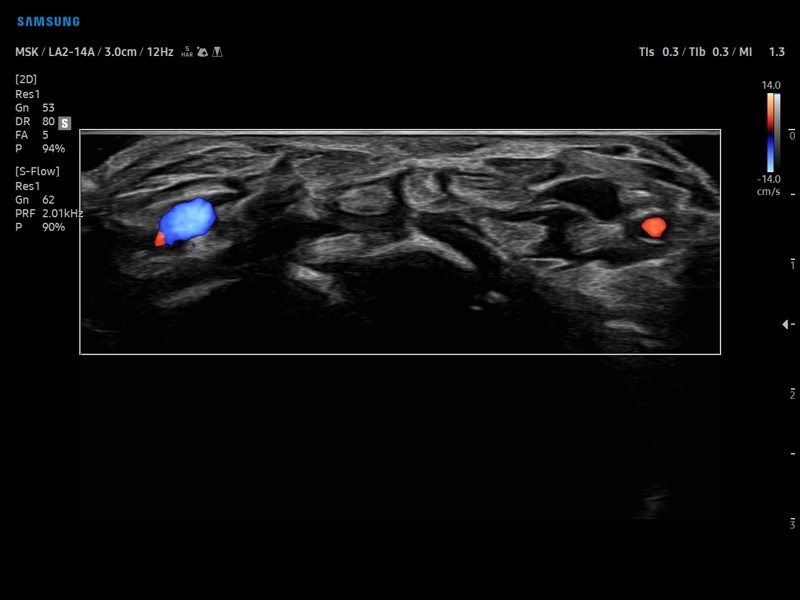

• Диагностика костно-мышечной системы

• Модуль MV-Flow – программа (режим), позволяющая визуализировать кровоток в микроциркуляторном русле с высоким разрешением без использования контраста.

• Программа SEE Stream – режим недопплеровской визуализации кровотока в реальном масштабе времени.

• Модуль MV-Flow - программа (режим), позволяющая визуализировать кровоток в микроциркуляторном русле с высоким разрешением без использования контраста.